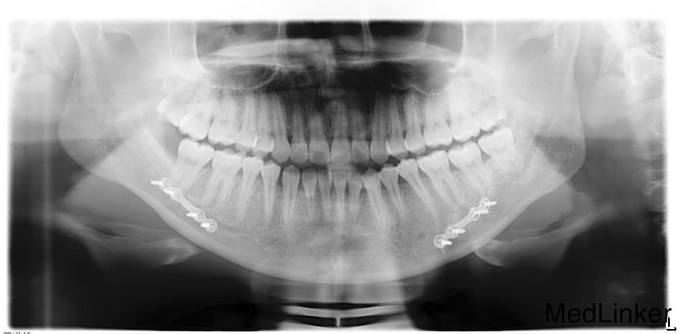

正颌术后半年余,患者2015年1月12日因“下颌偏斜10余年”来我院治疗,于2015年1月16日行“双侧下颌骨升支矢状劈开截骨前徙术+去骨皮质术+骨内坚固内固定术+上下颌牵引钉植入术”,今为取出下颌骨存留钛板来我院就诊,门诊以"正颌术后钛板存留"收入

诊断:正颌术后钛板留存,患者入院后完善相关检查,排除手术禁忌证,有手术指征,于2015年8月16日局麻下行“双侧下颌骨钛板钛钉取出术”,术后予消肿等对症治疗。